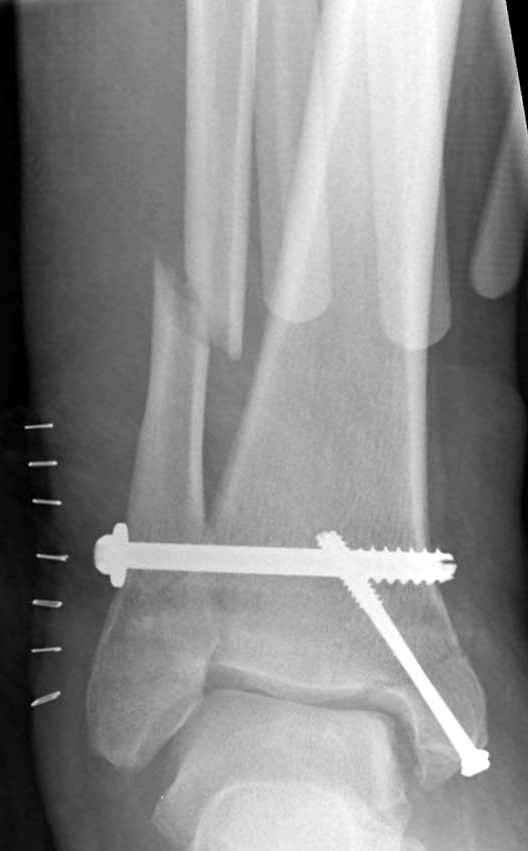

Ниже рентгенограммы

До операции 28 июля

Операция 29 июля

Через месяц

Боковой через месяц

15 ноября прямой

15 ноября боковой

15 ноября трехчетвертной

12 января прямой

12 января боковой

12 января трехчетвертной

Риторический вопрос - в каком руководстве рекомендован такой способ остеосинтеза наружной лодыжки?

Очевидно, такой результат операции был запрограммирован. При невосстановленной длине и практически нефиксированной малоберцовой кости (этот кортикальный винт - как карандаш в стакане), при неустраненном подвывихе, невправленной и тоже нефиксированной внутренней лодыжке нет стабильной вилки сустава. Если такую операцию сделать даже сразу, а не через 4 месяца, то результат ожидаем

тот же.

Вообще говоря, такое повреждение вполне успешно можно лечить без операции - если 6 недель подержать в гипсовом "сапожке" с хорошо устраненным подвывихом. Вероятное несращение внутренней лодыжки не обязательно компрометирует результат.

Ну а уж если выбран остеосинтез - нначать надо было с репозиции малоберцовой кости с точным восстановлением длины, с фиксацией треть-трубчатой пластиной по задней поверхности. Позиционный винт

избыточен - повреждение практически подсиндесмозное. А если бы

действительно было повреждение синдесмоза - в 4 месяца позиционный винт - не решение. Внутренню лодыжку такую - надо было бы спицами и проволочной петлей. Извините за эти банальности.

Вариант с артродезом уже обсудили. Хотя, после увиденых снимков, пессимизм насчет восстановительной операции у меня, например, несколько уменьшился. Особенного уж какого-то остеопороза не видно даже на январских снимках. Можно черед мини-доступы убрать винты, аппаратом вправить малоберцовую кость, устранить подвывих стопы. Ну а дальше фиксировать малоберцовую пластиной сзади. А может, и напряженной Y-спицей попробовать - Анатолий Федорович, как Вы полагаете? Внутреннюю - то, что осталось, если уже не получится сделать спицами и проволокой, то что-то типа пластики дельтовидной связки. А может, и не трогать ее вовсе... В общем, выбор непростой,

много факторов надо взвесить.

Если до сих ничего не сделано, с артродезом сустава в данный момент я бы повременил, на выставленных январских снимках хорошо сохранившийся сустав, а в "мортиз" (трехчетвертной) и на боковых снимках не менее 5 мм укорочение малоберцовой кости. Косые переломы лучше фиксировать пластинами, как то мы разбирали случай, где было отмечено, что это закон "таранная кость всегда следует за малоберцовой".

С подобным случаем приходилось сталкиваться у гормонозависимого пациента с 4 месячным подобным переломом после безуспешного лечения в аппарате Илизарова. Вальгусная стопа, остеопороз, диастаз в медиальной лодыжке. Произвел открытую репозицию мед лодыжки, синтез тяговым винтом 3.5 мм из титана, костную пластику спонгиозой, до 2 см куб из надлодыжечной зоны. Затем остеотомия по линии перелома малоберцовой кости узким долотом из 0.5 см доступа и ручная коррекция вальгуса . Блокирующий винт через обе кости. Остеосинтез по MIPO технологии пластиной 1-3 трубки. Внешней фиксации не применялось, перелом сросся за три месяца. Согласен с д-ром Кульжановым, без пластины в подобных случаях не обойтись.

Делались ли сравнительные снимки, оба сустава в фас на одной пленке? Если с них сделать скиаграммы и наложить их, будет видно, удалось ли устранить наружный подвывих стопы.

Вообще-то начинать надо бы с восстановления длины малоберцовой кости. Вряд ли возможно сделать первой репозицию внутренней лодыжки точно, в таком сроке местных ориентиров нет. Соответственно, смещение внутренней лодыжки кнаружи только уменьшается, но не ликвидируется полностью. Тогда и таран из наружного подвывиха не удается полностью вывести.

тарнная кость находится в латеральном подвывихе, что снижает шансы этого сустава.

Это видно по снимку - середина суставной поверхности тарана должна быть против середины суставной поверхности тибии. Причины, что это не так:

1. Внутренняя лодыжка не на месте

2. наружная лодыжка укорочена

3. Возможно есть компрессионный перелом наружной части пилона тибии.

В подобных случаях лучше всего начинать с главной цели - вправить таран, временно зафиксировать спицами и используя таран как шаблон поставить на место лодыжки, неважно в какой последовательности.

В данной ситуации я бы переделал или\и начал бы объснять пациенту что такое протезирование голеностопного сустава и артродез.